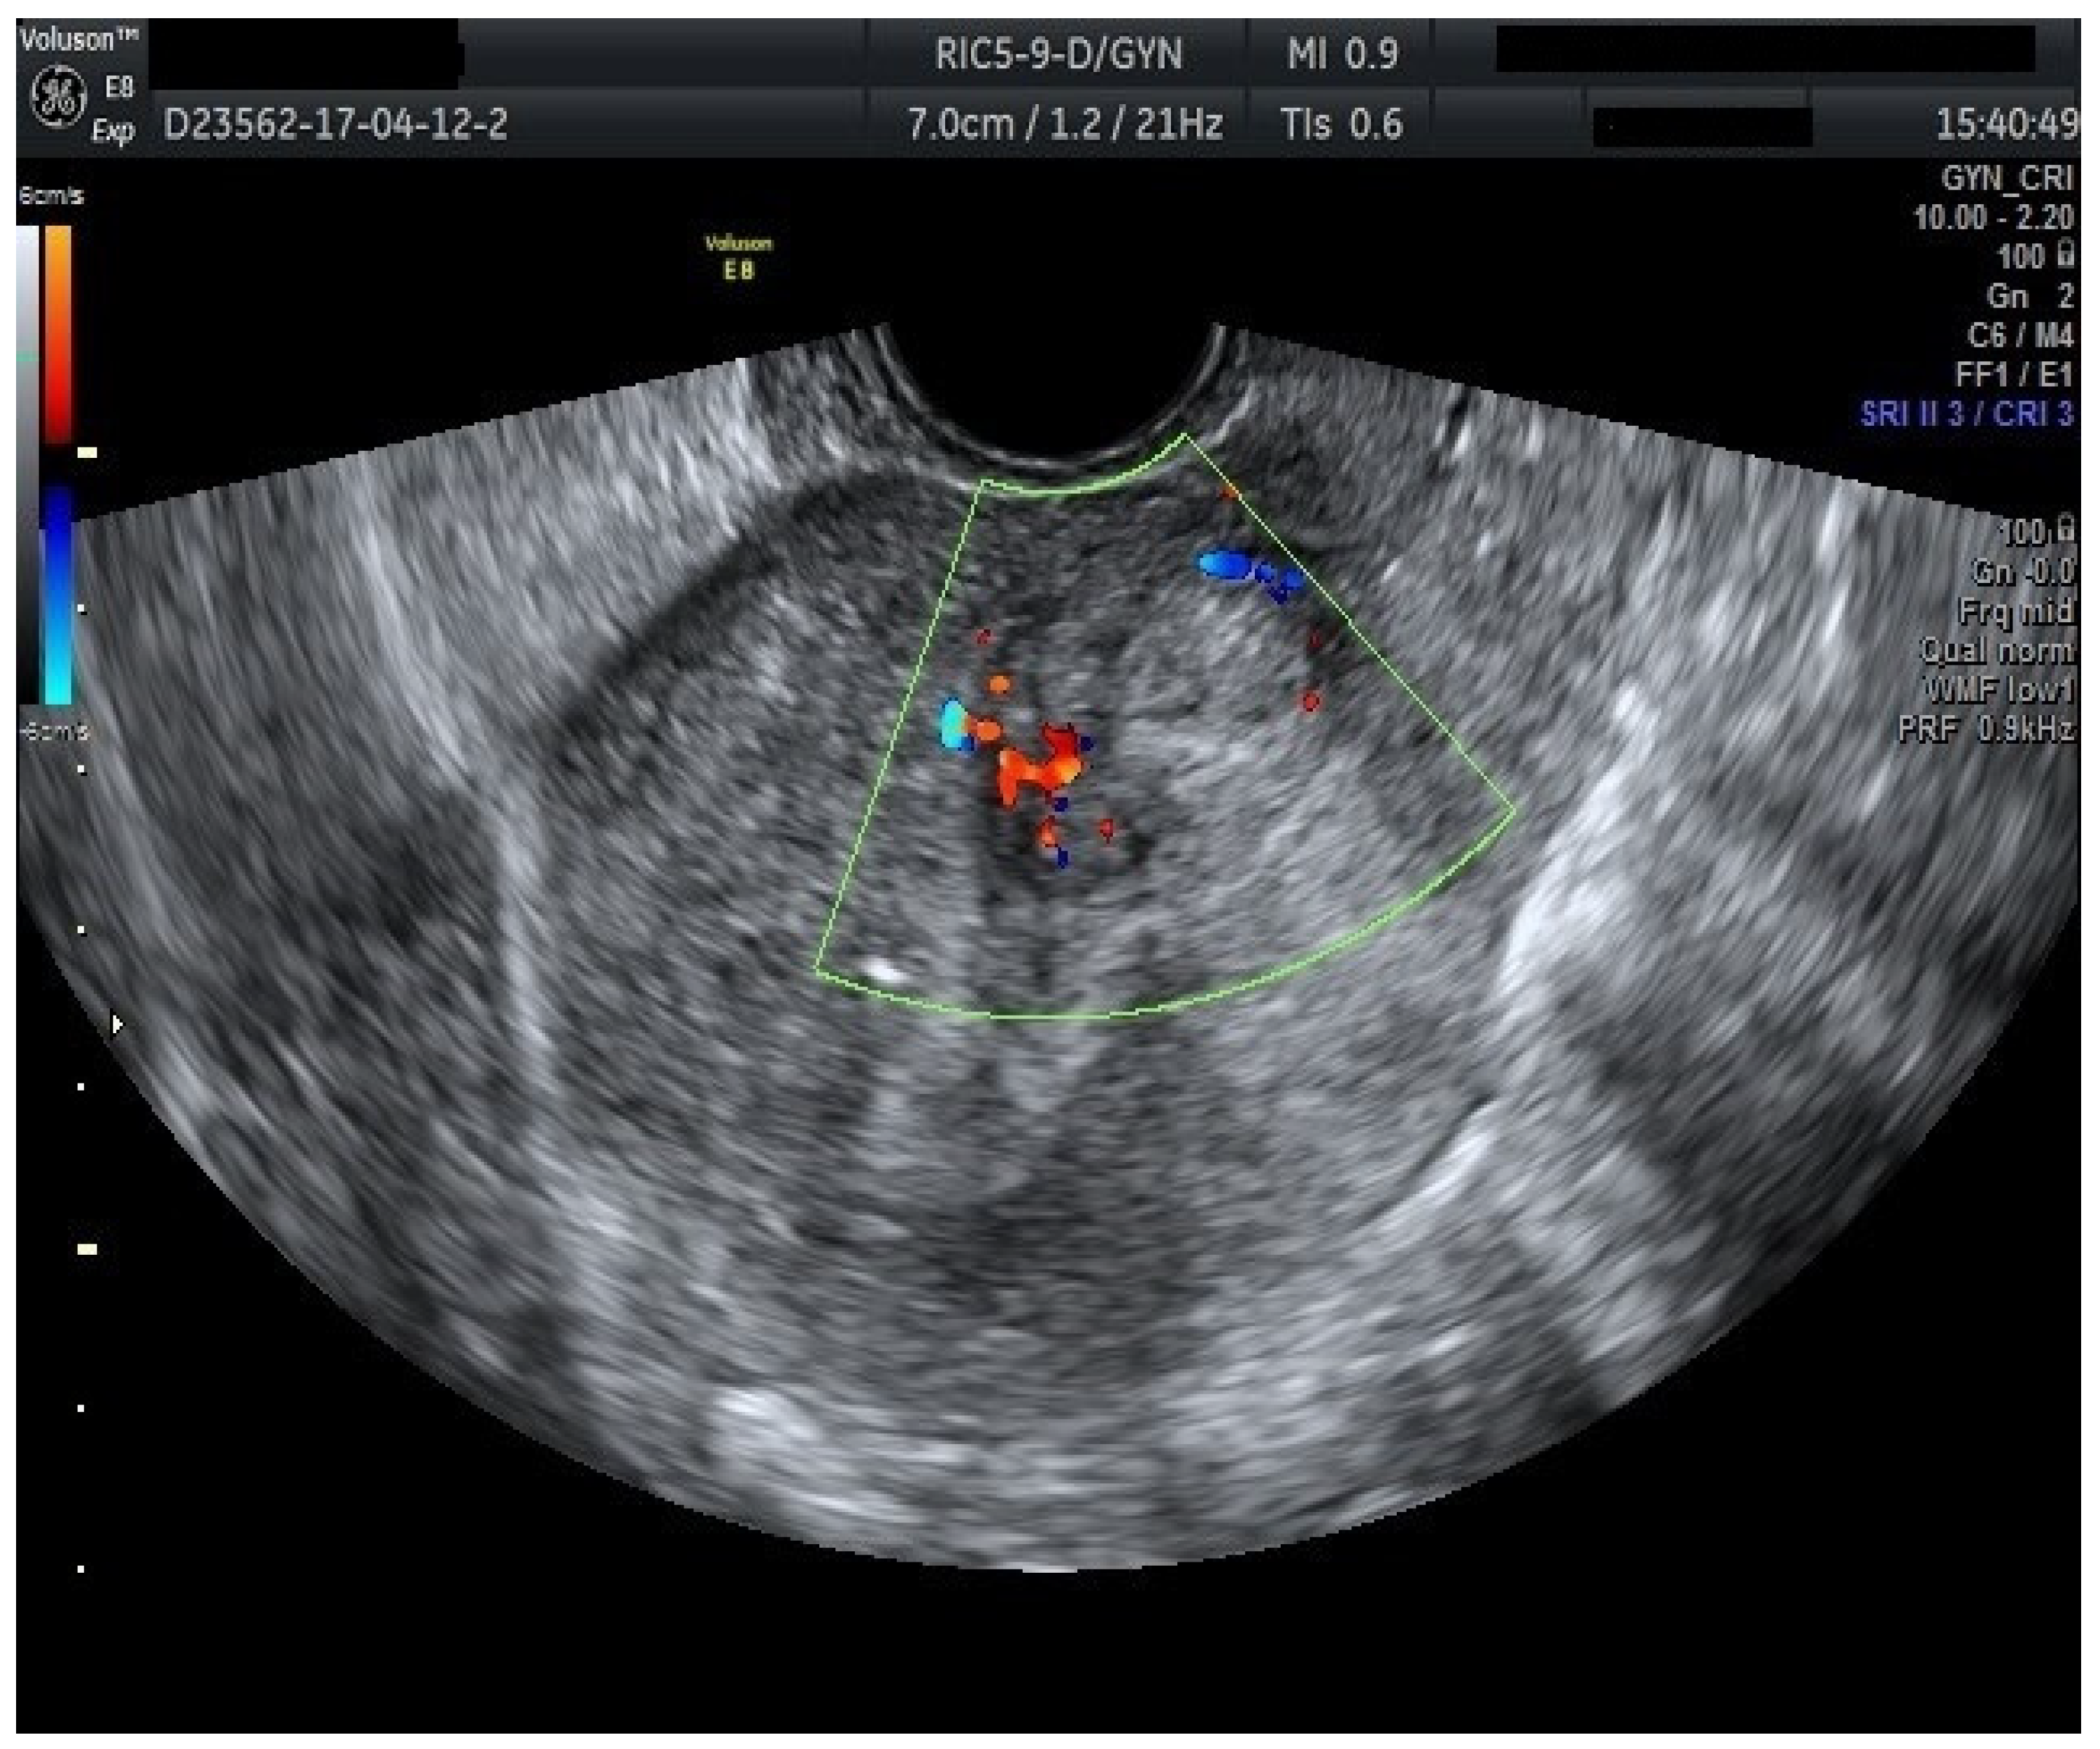

Figure 9. Color Doppler vascular score 4 in endometrial cancer.

Regarding the color Doppler assessment, a vascular score of 1 usually excludes endometrial cancer, with a sensitivity of 87.5% and a specificity of 79% (Figure 8). This is due to the presence of a high number of newly formed vessels in malignant tumors (Figure 9).

Furthermore, color Doppler imaging proved valuable in more accurately determining myometrial invasion. The predominant feature of blood vessels in endometrial cancer was the presence of scattered vessels (Figure 10), which demonstrated a sensitivity of 50% (95% CI: 0.2152 to 0.7848) and a specificity of 94.74% (95% CI: 0.8563 to 0.9819). Additional vascular aspects indicative of endometrial cancer were the presence of vessels with various branches (Figure 11) and color splashes (Figure 12).